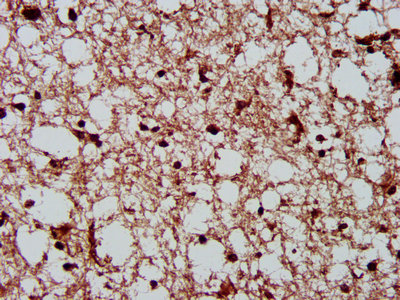

IHC image of CSB-PA006072LA01HU diluted at 1:300 and staining in paraffin-embedded human brain tissue performed on a Leica BondTM system. After dewaxing and hydration, antigen retrieval was mediated by high pressure in a citrate buffer (pH 6.0). Section was blocked with 10% normal goat serum 30min at RT. Then primary antibody (1% BSA) was incubated at 4°C overnight. The primary is detected by a biotinylated secondary antibody and visualized using an HRP conjugated SP system.

IHC image of CSB-PA006072LA01HU diluted at 1:300 and staining in paraffin-embedded human colon cancer performed on a Leica BondTM system. After dewaxing and hydration, antigen retrieval was mediated by high pressure in a citrate buffer (pH 6.0). Section was blocked with 10% normal goat serum 30min at RT. Then primary antibody (1% BSA) was incubated at 4°C overnight. The primary is detected by a biotinylated secondary antibody and visualized using an HRP conjugated SP system.